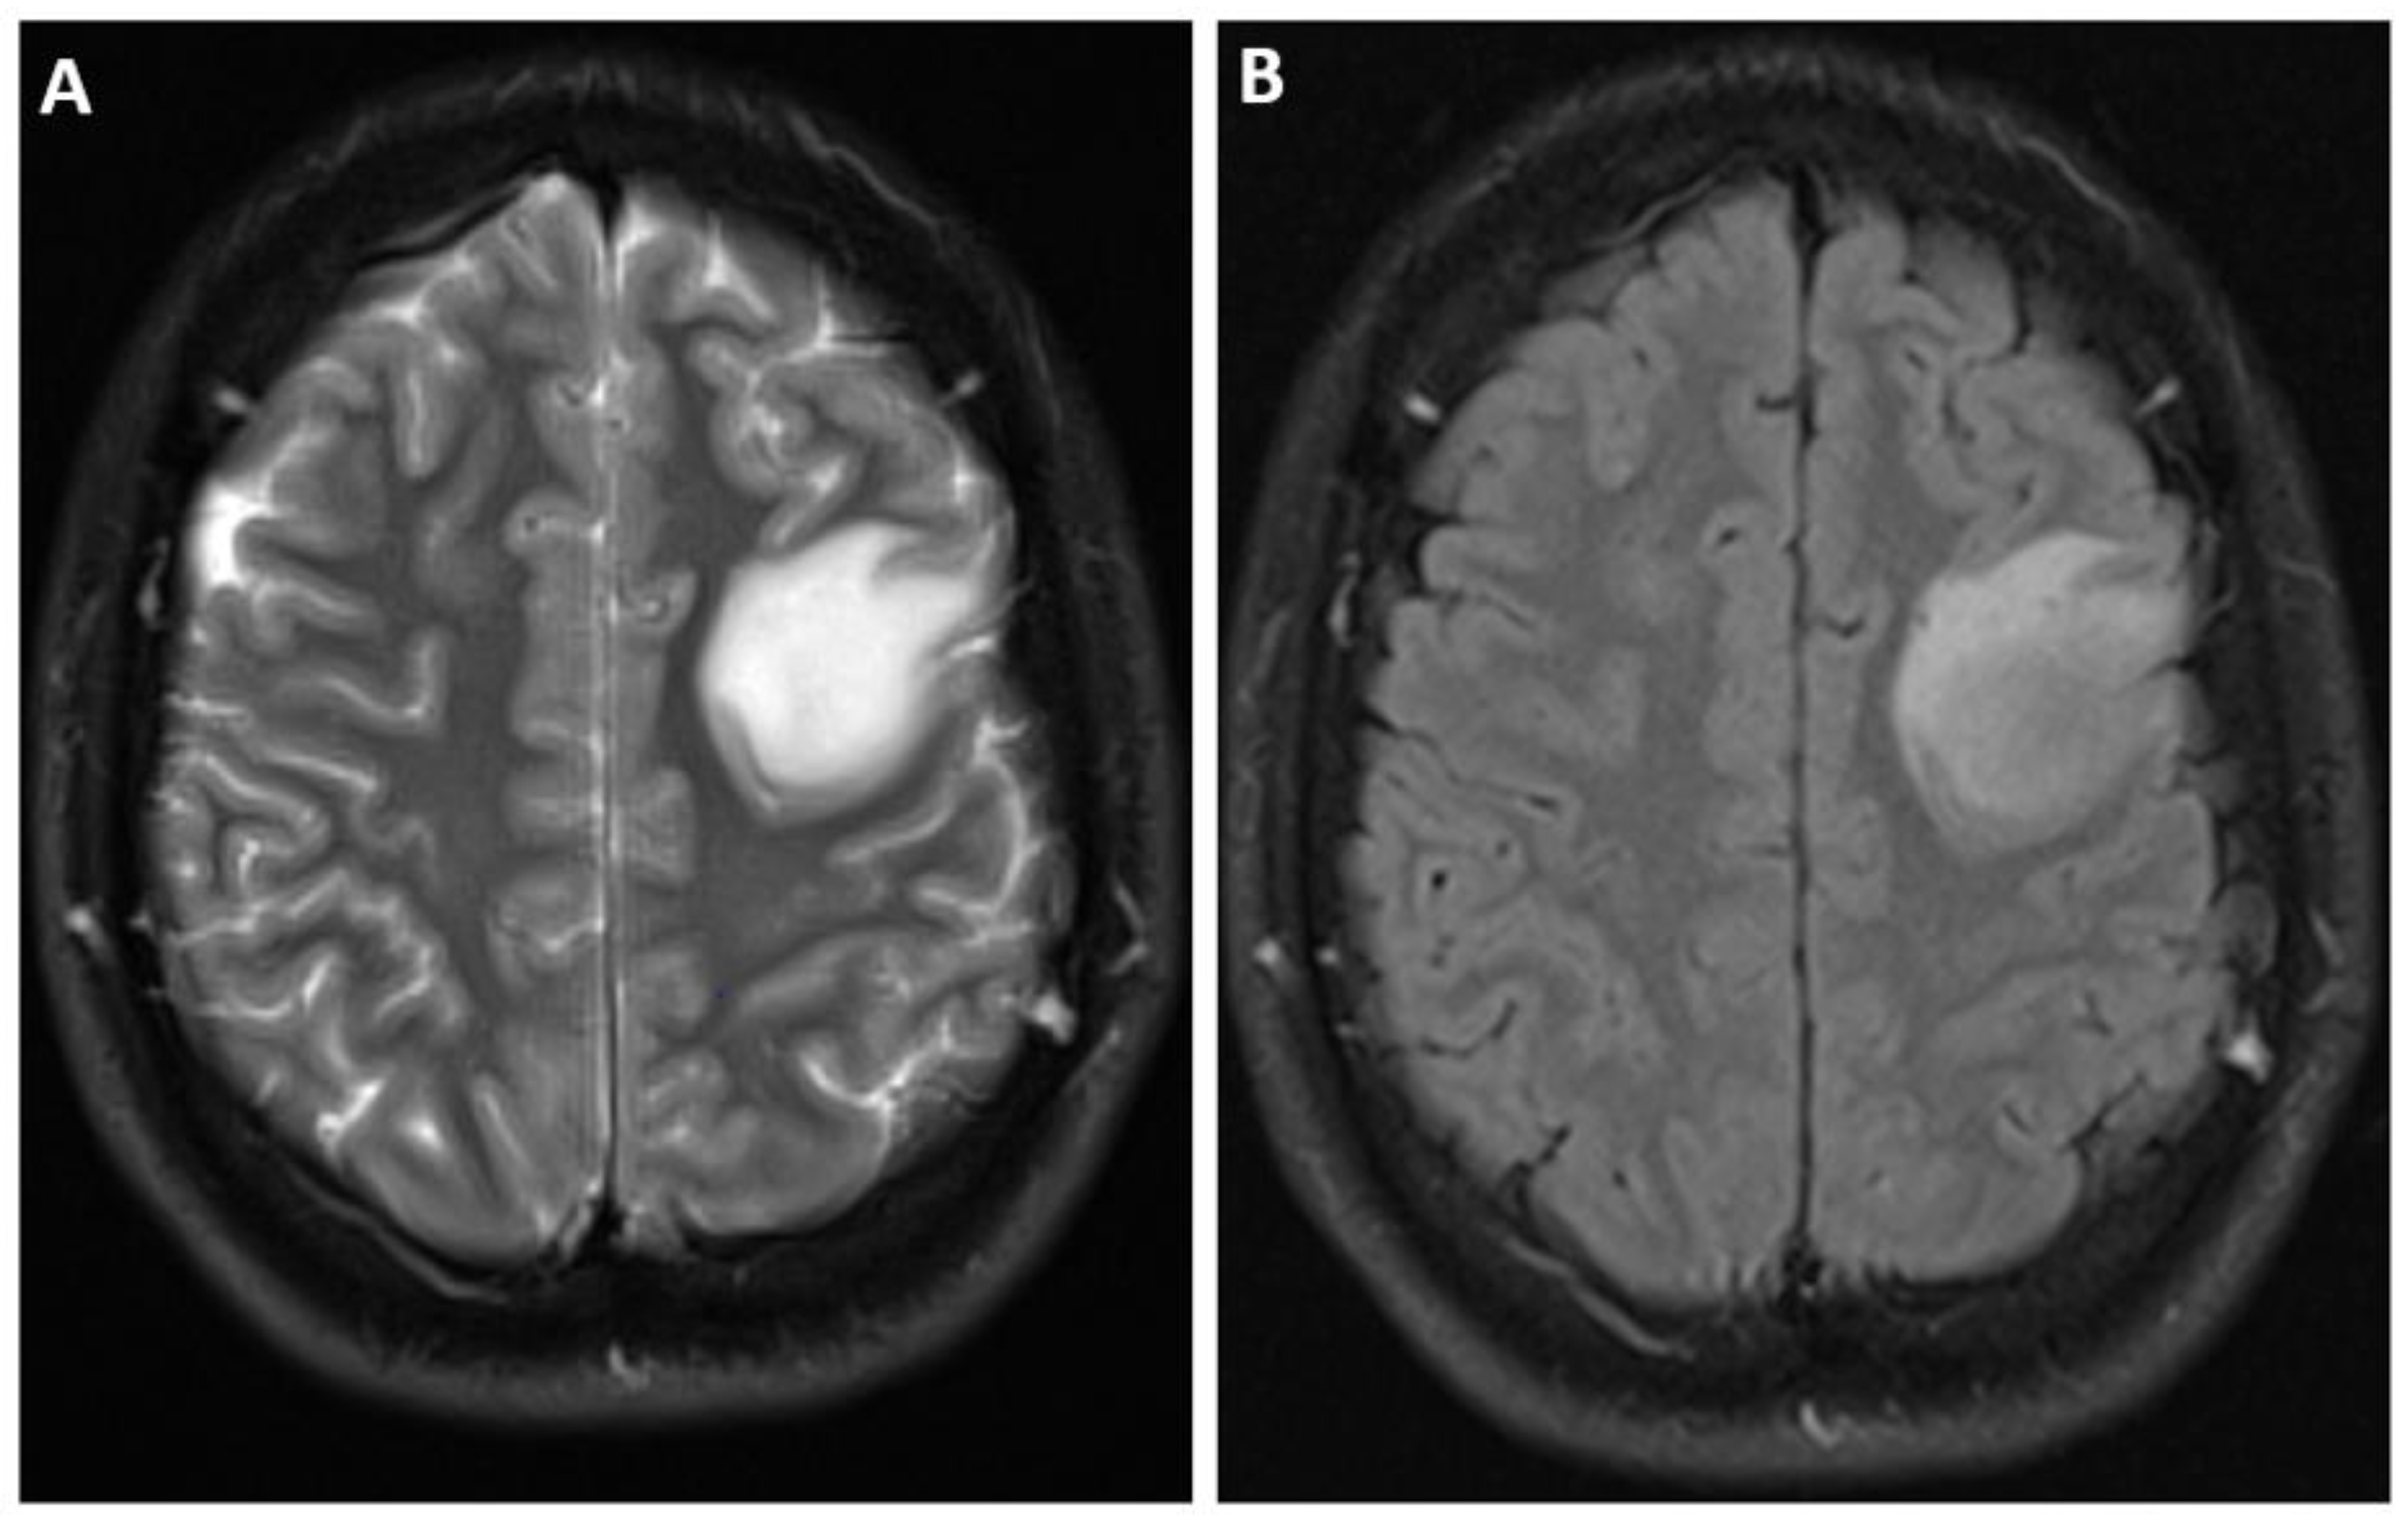

- Patel, S.H.; Poisson, L.M.; Brat, D.J.; Zhou, Y.; Cooper, L.; Snuderl, M.; Thomas, C.; Franceschi, A.M.; Griffith, B.; Flanders, A.E.; et al. T2–FLAIR Mismatch, an Imaging Biomarker for IDH and 1p/19q Status in Lower-grade Gliomas: A TCGA/TCIA Project. Clin. Cancer Res. 2017, 23, 6078–6085. [Google Scholar] [CrossRef]

- Mohammed, S.; Ravikumar, V.; Warner, E.; Patel, S.; Bakas, S.; Rao, A.; Jain, R. Quantifying T2-FLAIR Mismatch Using Geographically Weighted Regression and Predicting Molecular Status in Lower-Grade Gliomas. Am. J. Neuroradiol. 2022, 43, 33–39. [Google Scholar] [CrossRef]

- van Garderen, K.A.; Vallentgoed, W.R.; Lavrova, A.; Niers, J.M.; de Leng, W.W.; Hoogstrate, Y.; de Heer, I.; Ylstra, B.; van Dijk, E.; Klein, S.; et al. Longitudinal char-acteristics of T2-FLAIR mismatch in IDH-mutant astrocytomas: Relation to grade, histopathology, and overall survival in the GLASS-NL cohort. Neuro-Oncol. Adv. 2023, 5, vdad149. [Google Scholar] [CrossRef]

- Juratli, T.A.; Tummala, S.S.; Riedl, A.; Daubner, D.; Hennig, S.; Penson, T.; Zolal, A.; Thiede, C.; Schackert, G.; Krex, D.; et al. Radiographic assessment of contrast en-hancement and T2/FLAIR mismatch sign in lower grade gliomas: Correlation with molecular groups. J. Neuro-Oncol. 2019, 141, 327–335. [Google Scholar] [CrossRef] [PubMed]

| Astrocytoma, IDH-mutant | IDH1, IDH2, ATRX, TP53 | CDKN2A/B homozygous deletion designated grade 4, no IDH-wildtype | Homogenous, circumscribed, T2-FLAIR mismatch sign |